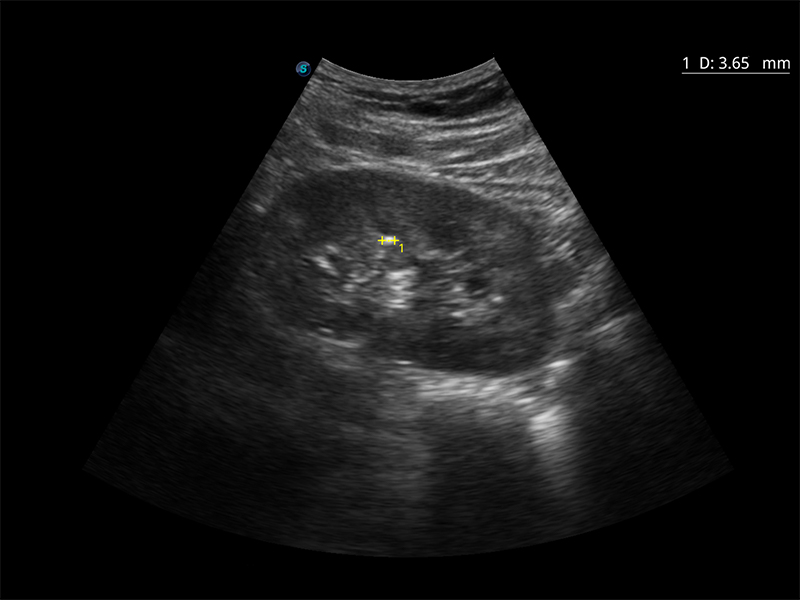

Funkcja Auto IMT

Automatyczny obrys Auto Trace